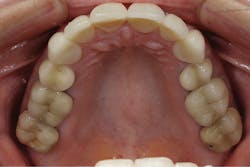

My diagnosis was that the final anterior restorations induced an anterior constriction. Her mandible was forced posteriorly from overcontoured excess lingual porcelain on teeth Nos. 7–10. In addition, her tongue did not have enough room to move forward for proper speech enunciation, especially with her s sounds. The initial treatment involved placing the patient in a Kois Deprogrammer appliance. 1 This would allow her mandible to move in a position dependent on the muscles and remove the interferences caused by her dentition and the excess lingual porcelain. The patient returned one week after wearing the appliance and stated that she felt great, her jaws were comfortable, and she liked their position. Diagnostic models were taken in her centric relation position with the appliance in place and mounted on a Panadent articulator. A diagnostic equilibration was completed on the models. The final equilibration would be completed after an additional three weeks.

Figure 3: Maxillary occlusal view of the patient’s original restoration